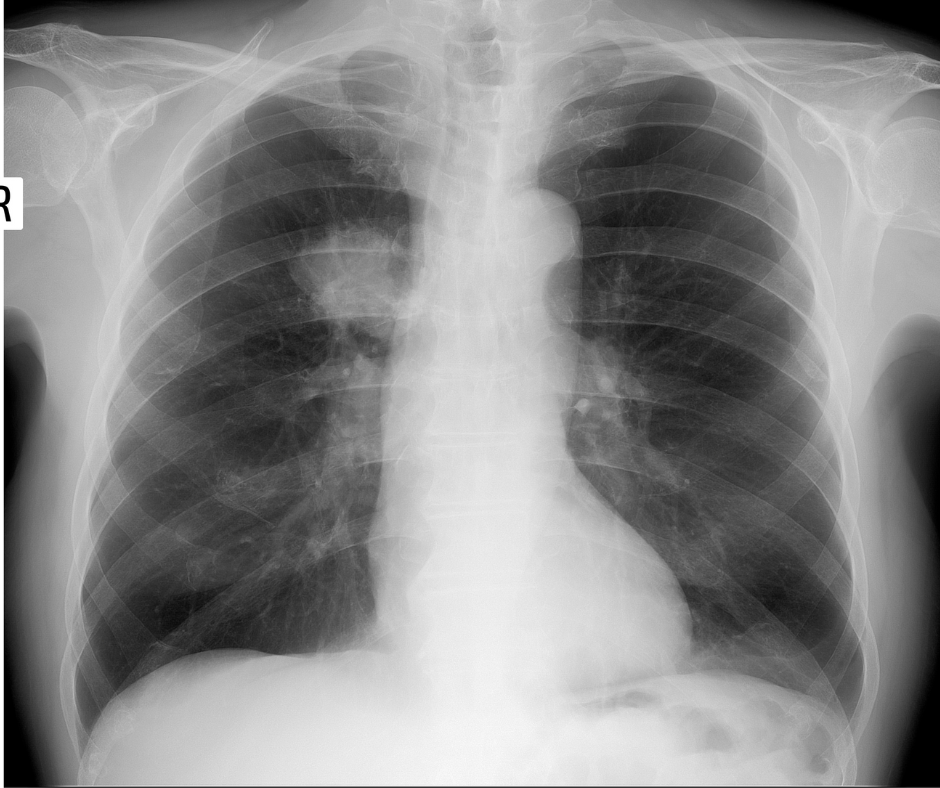

In a recent video interview, two radiology professors from the Yale School of Medicine discussed the impact of the iodinated contrast media (ICM) shortage and potential strategies, ranging from ICM dose reduction to possible deferment of non-urgent imaging, that may provide a viable path moving forward.